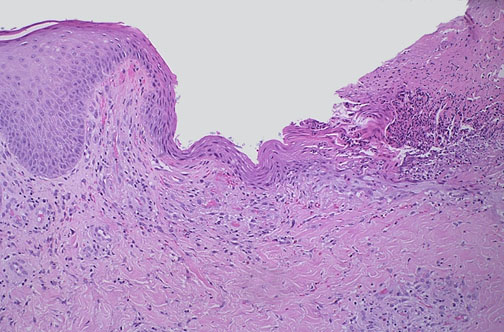

| The bite of the brown recluse spider (Loxosceles spider) initially produces a mild stinging sensation, but within hours there is intense pain along with erythema and then bulla formation. This can be followed by formation of a deep ulcer with necrotic base. Most of these ulcerative lesions will heal spontaneously, though weeks to months may pass, and some require debridement or skin grafting. |